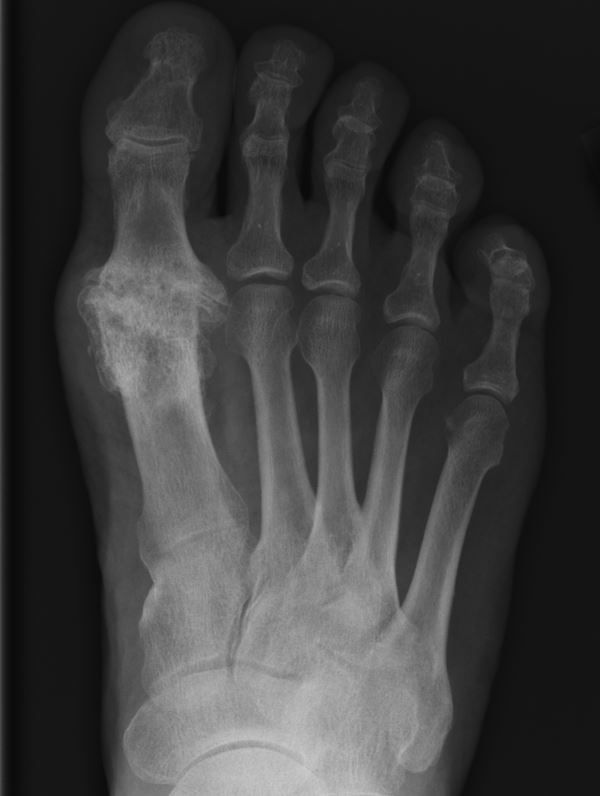

Home Schwerpunkte Krankheitsbilder Arthrose der Großzehe (Hallux Rigidus) GGG Arthrose Kellgren 4 massiv! Rö dp

GGG Arthrose Kellgren 4 massiv! Rö dp

schwere ARthrose Großzehegrundgelenk im Röntgen